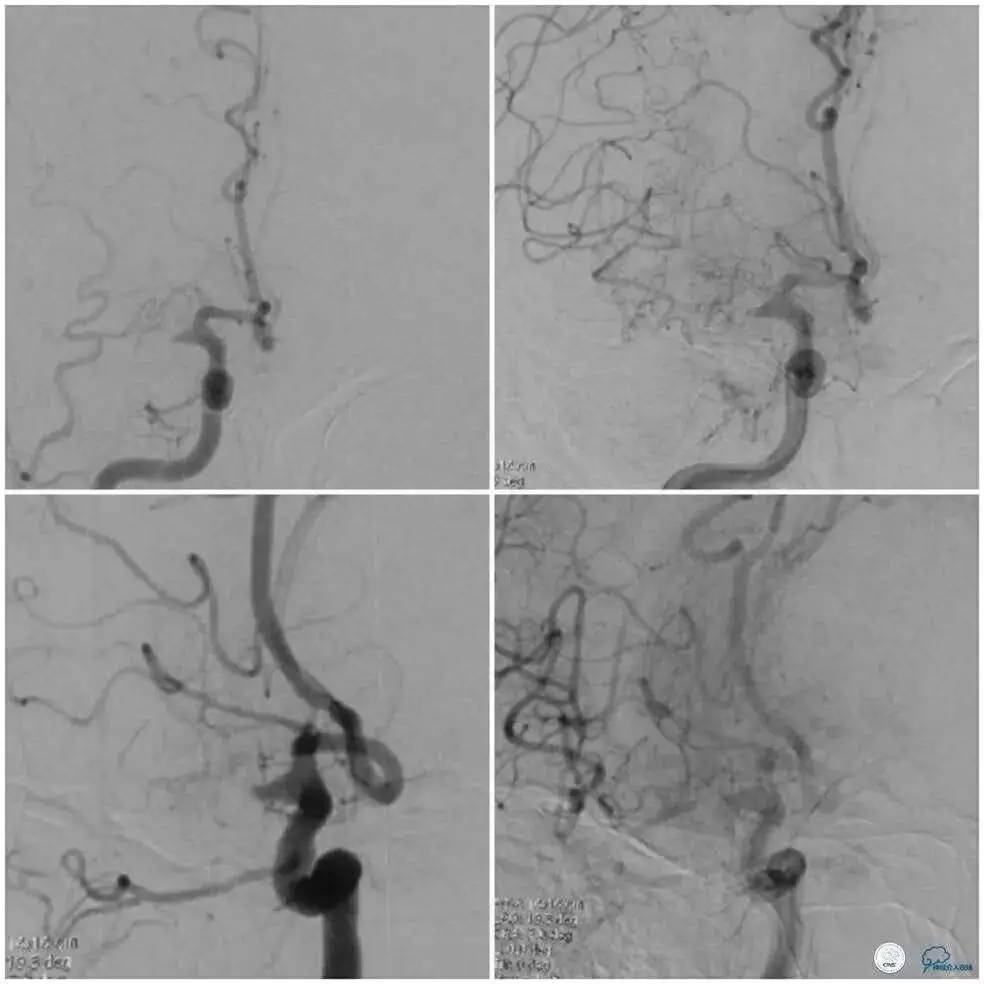

术前DSA示右侧大脑中动脉极重度狭窄,动脉早期类似闭塞改变,前向血流减慢,动脉晚期接近实质期可以见病变远端显影(图1)。

同侧大脑后动脉及大脑前动脉提供的软脑膜动脉侧支代偿欠佳(图1及图2)。